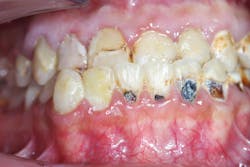

No. 1: Initial phase

- Periodontal therapy with scaling and chlorhexidine rinse

No. 2. Maxillary arch

- Extraction of nonrestorable tooth no. 3

- Endodontics, post, and core buildup with Rebilda DC (Voco)

- Selective etching, bonding with Futurabond DC, restoration with GrandioSO

- Provisional crowns fabricated using Structure 2 (Voco; figure 2)